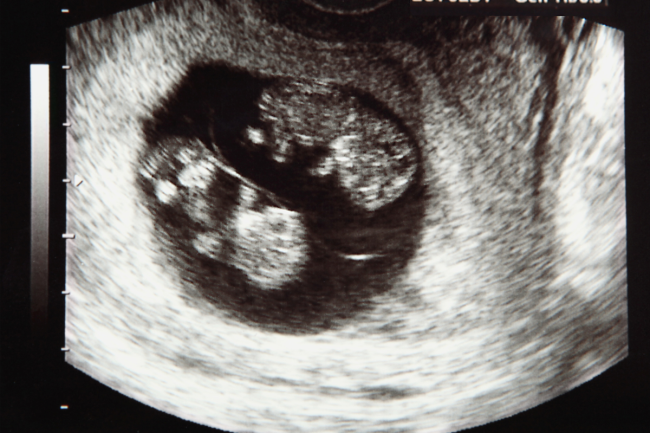

The Different Types of Twins Explained

Reading Time: 5 minutesEver heard someone ask, “Do twins run in your family?” or even, “Are they identical?” when referring to a set of boy/girl twins (gasp!)? These curious bystanders at the store mean well, but they are probably just asking the same ol’ twin questions they ask everyone. Where the most common types of twins are identical…